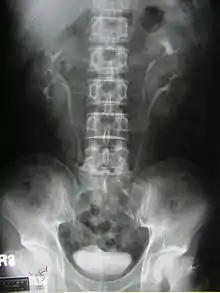

Duplicated ureter

Duplicated ureter or Duplex Collecting System is a congenital condition in which the ureteric bud, the embryological origin of the ureter, splits (or arises twice), resulting in two ureters draining a single kidney. It is the most common renal abnormality, occurring in approximately 1% of the population.[1][2]